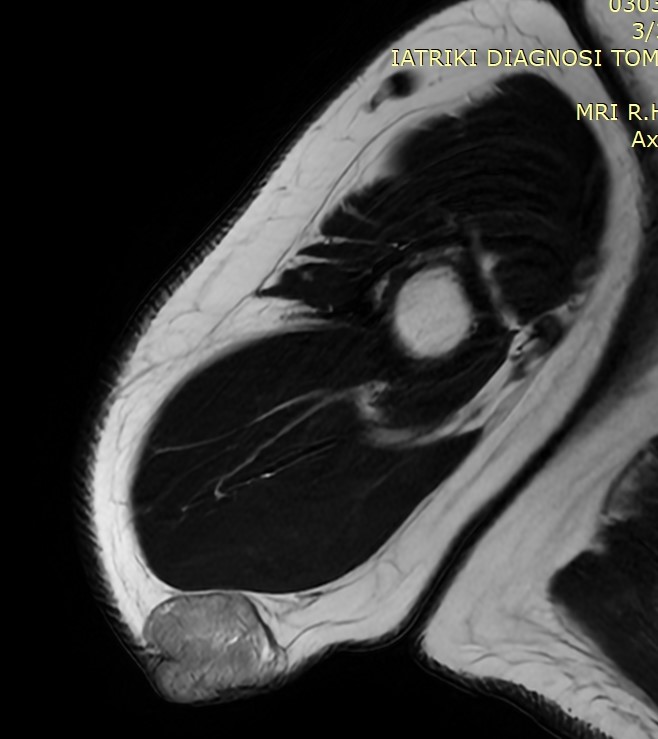

MRI μηροβουβωνικής πτυχής με σκιαγραφικό, που αναδεικνύει μαλακοτισθενή μάζα εκφυόμενη από τη μεγάλη σαφηνή φλέβα (Ευγενική παραχώρηση Dr. V. Penopoulos)